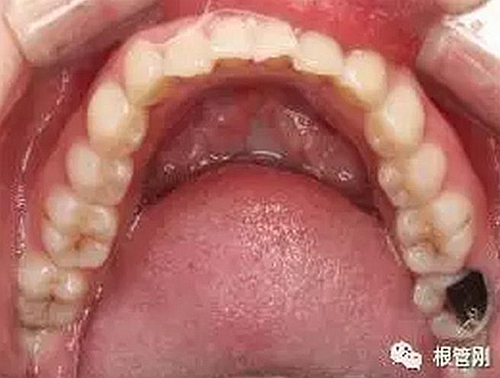

這是一顆嚴重的蛀牙,顏色發(fā)黑,牙齒的一半已經(jīng)崩解,看到此情此景,也許很多人會想它的神經(jīng)肯定死掉了吧?它還有救嗎?應該會做根管治療+牙冠修復吧?

3.jpg

4.jpg